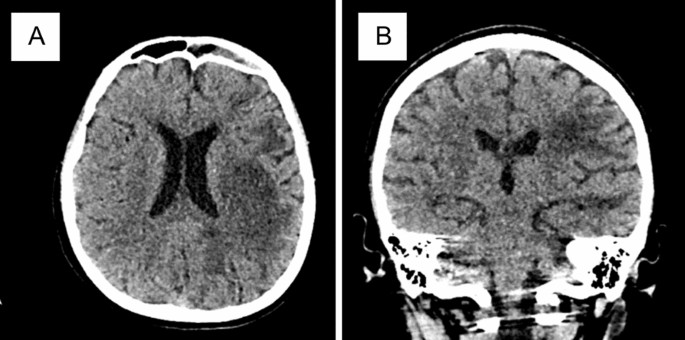

During physical examination in the ICU, the patient was sedated and intubated with a Glasgow coma scale of E2M4VT. Oxygen saturation was 93–100% on a ventilator with FiO2 40%. There were clubbed fingers, as well as an increase in physiological reflex on the right side, positive nuchal rigidity, and positive Babinski reflex on the right side. Peripheral blood laboratory revealed leukocytosis of 1706 × 109/L. Head CT scan revealed diffuse brain swelling (Fig. 2). Cerebrospinal fluid analysis for leukocytes and protein was elevated and glucose levels were decreased, indicating bacterial meningitis. The cerebrospinal fluid culture showed no growth of microorganisms. The patient had a weakly positive antinuclear antibody (ANA) test, a weakly positive lupus anticoagulant test, and an anti-ds-DNA 2.4 test result.

Second patient’s head CT: A hypodense lesion on the subcortical frontotemporoparietooccipital left lobe and B frontal right lobe